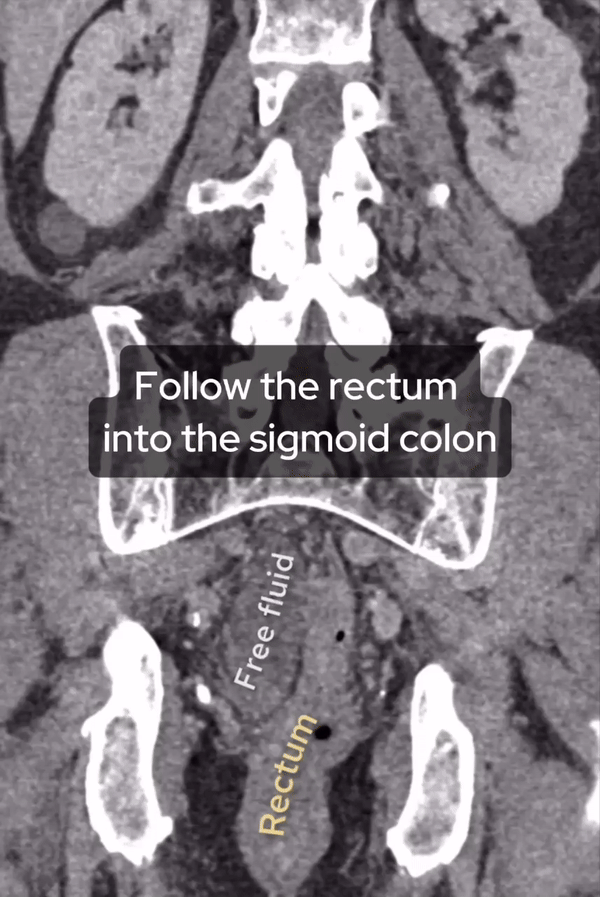

You’ve seen the axial slices but below I’ve shown coronal slices of the same CT, here’s what we see:

1. The rectum, positioned normally in the pelvis.

2. Free fluid in the pelvis, lateral to the rectum.

3. Following the bowel, there’s a whirling appearance in the sigmoid colon, consistent with the site of torsion.

4. A dilated bowel loop proximal to the whirl sign.

This is a textbook case of sigmoid volvulus. Now you’ve seen this review for ischaemia by looking for gas within the bowel wall and lack of enhancement whilst check lung windows to make sure there is no extraluminal gas representing a perforation.

Follow the rectum through – you will first see a whirl within the sigmoid before finding dilated obstructed sigmoid proximal to this, accounting for the X-Ray finding.